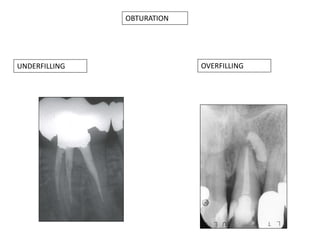

OBTURATION

UNDERFILLING

OVERFILLING